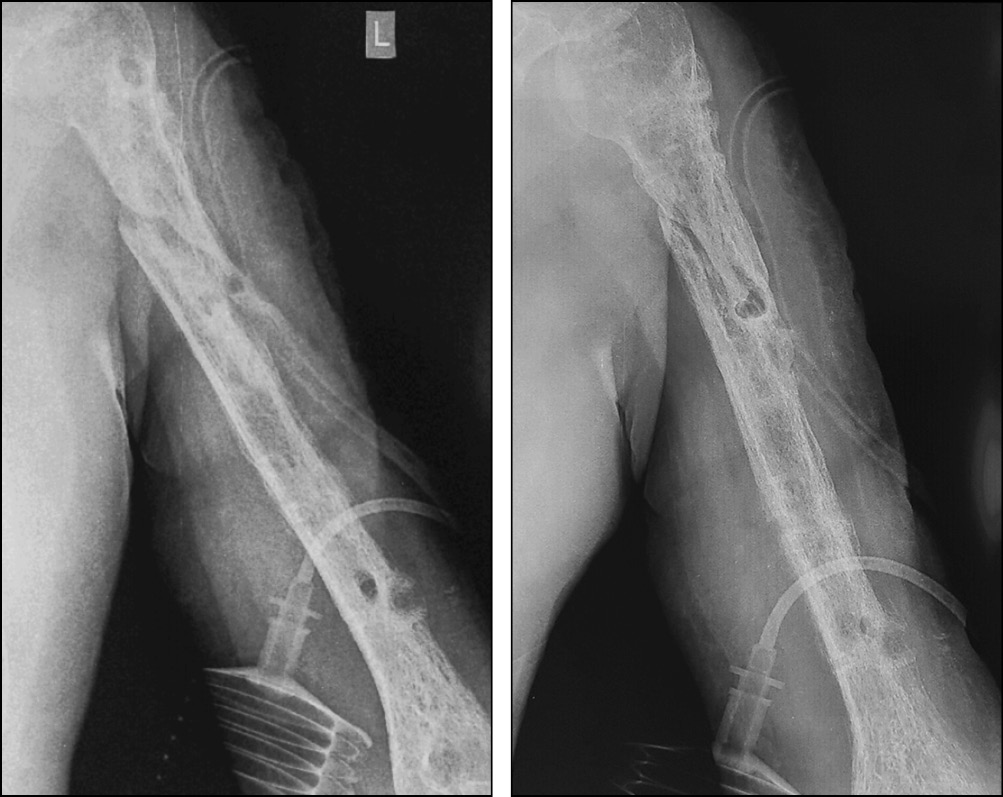

Пациент наблюдался амбулаторно 1 раз в месяц, разрабатывал движения в плечевом и в локтевом суставах. Через 7 мес. диагностирована консолидация области перелома левой плечевой кости, поле чего аппарат был демонтирован (рис. 8, 9), рецидивов за весь период наблюдения не зафиксировано. Функциональность конечности полностью восстановлена (рис. 10, 11).

Рис. 8. Рентгенограммы до демонтажа аппарата. Сросшийся перелом на границе проксимального и среднего отдела левой плечевой кости

Рис. 9. Рентгенограммы левой плечевой кости после демонтажа аппарата внешней фиксации